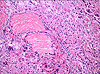

CASO N° 3 (Dr. Abel e Dr. Delgado)

Paciente do gênero masculino, 21 anos de idade, apresenta uma lesão no palato duro.